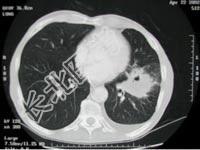

- 单项选择题男性患者,78岁, 吸烟50余年,近1年来常干咳, 来院就诊时行胸部CT检查,结果如图所示, 最有可能的诊断是 ( )

C、左肺癌

D、右肺癌